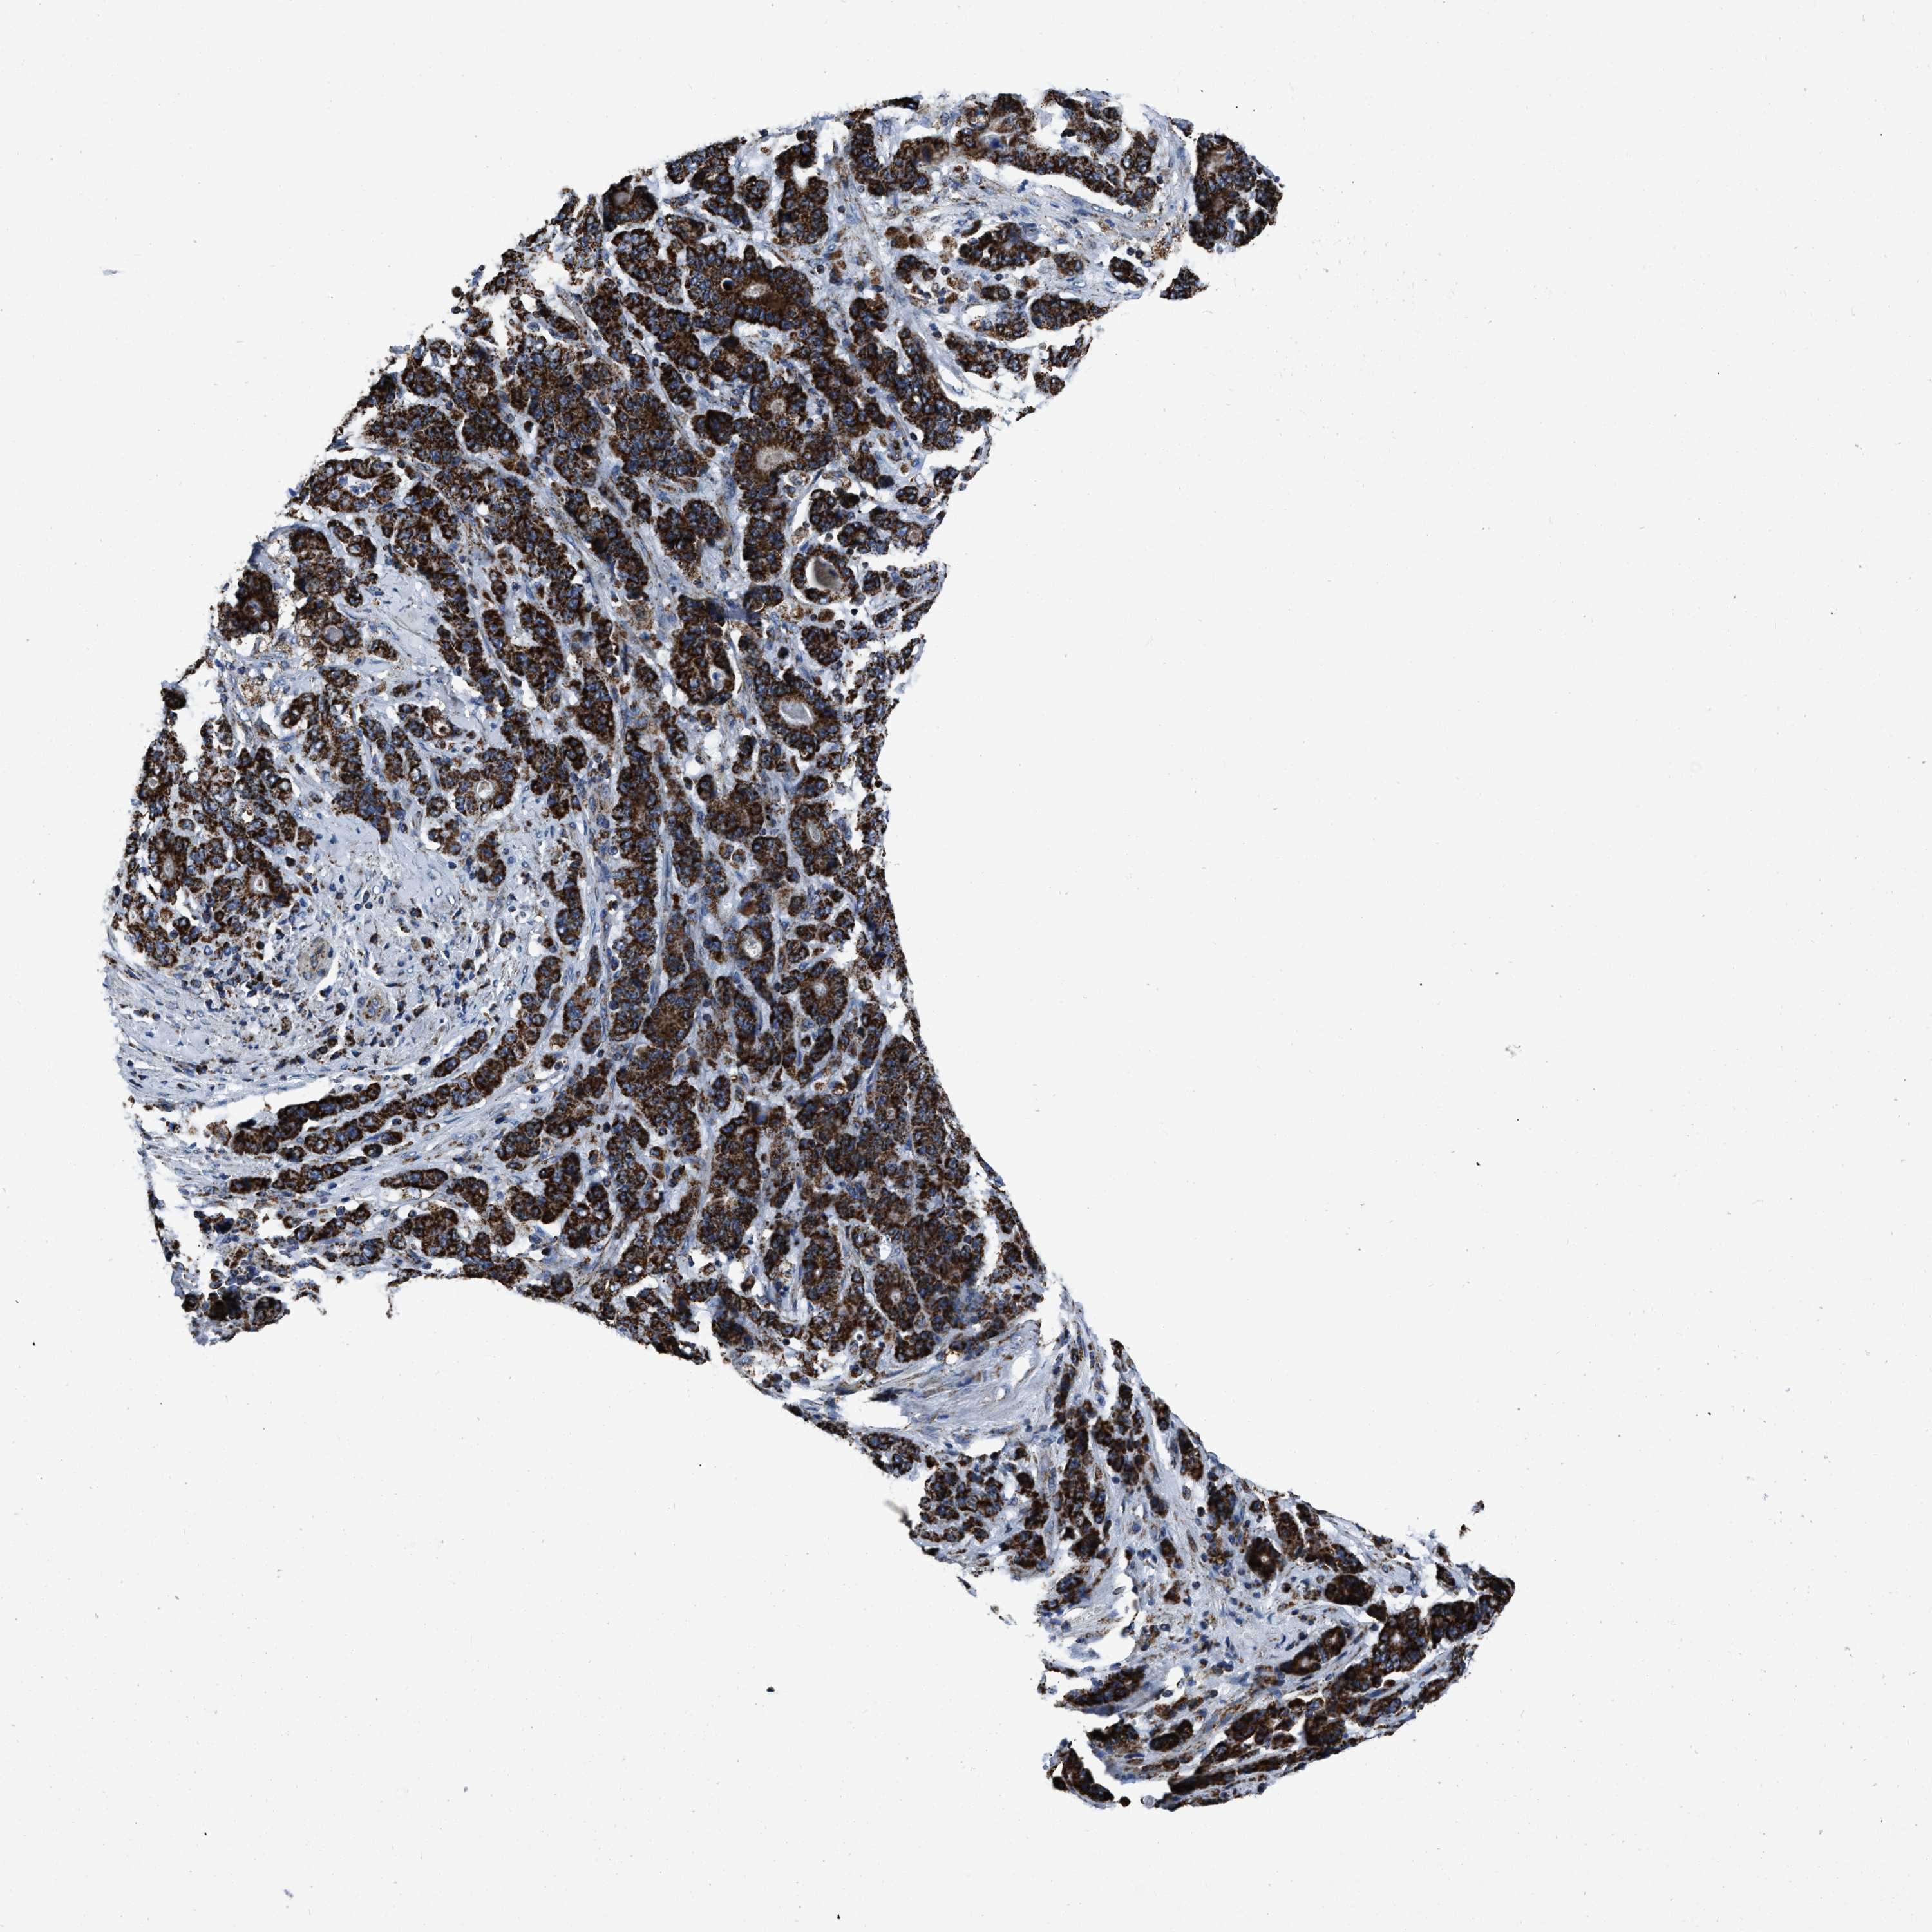

STOMACH CANCER - Protein expressioni

A mouse-over function shows sample information and annotation data. Click on an image to view it in a full screen mode. Samples can be filtered based on level of antibody staining by selecting one or several of the following categories: high, medium, low and not detected. The assay and annotation is described here.

Antibody stainingi

Antibody staining in the annotated cell types in the current human tissue is reported as not detected, low, medium, or high, based on conventional immunohistochemistry profiling in selected tissues. This score is based on the combination of the staining intensity and fraction of stained cells.

Each image is clickable and will lead to virtual microscopy that enables deeper exploration of all samples and also displays staining intensity scores, fraction scores and subcellular localization as well as patient and tissue information for each sample.

Antibody HPA018893

Staining

High

Medium

Low

Not detected

Intensity

Strong

Moderate

Weak

Negative

Quantity

>75%

75%-25%

<25%

None

Location

Nuclear

Cytoplasmic/membranous

Cytoplasmic/membranous,nuclear

Adenocarcinoma, NOS